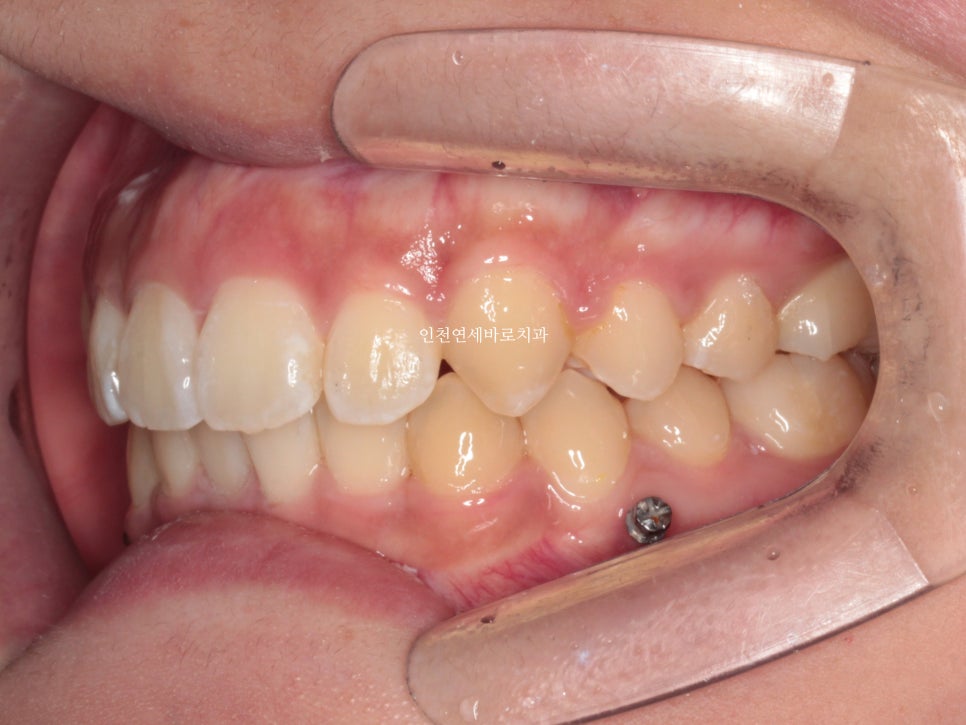

2년 후 역시 잘 유지되고 있으며

지난 주 왔을때의 모습입니다. 역시 잘 유지되고 있습니다.

긴밀한 교합과 배열로 잘 유지되고 있다고 판단됩니다.